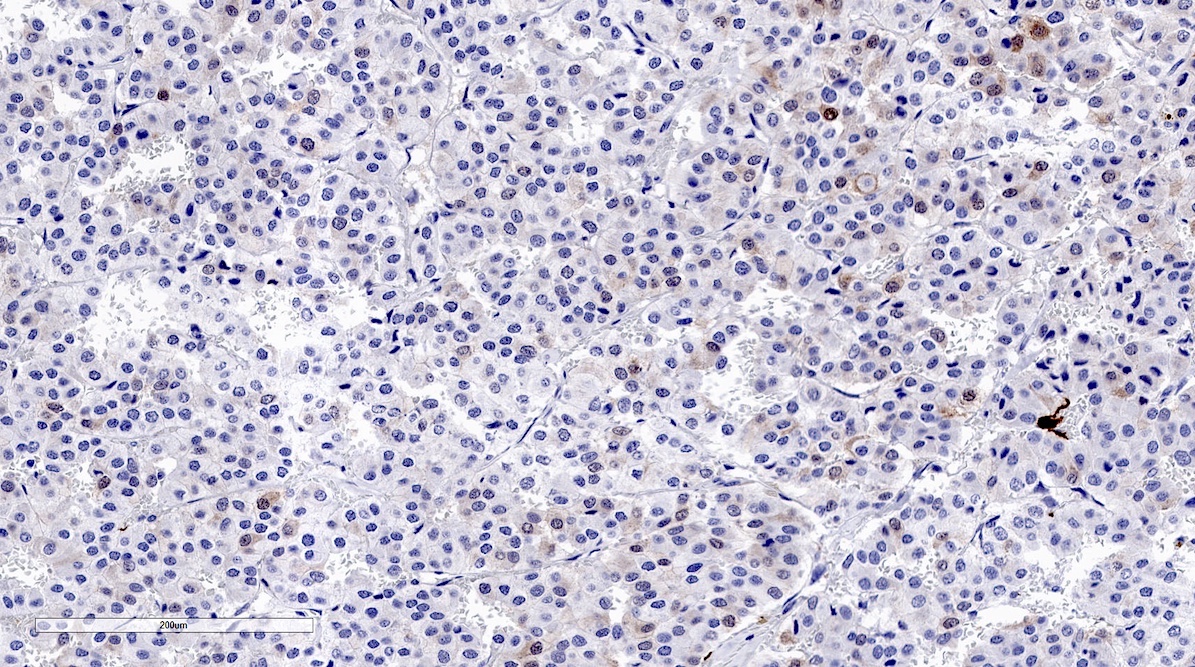

Microscopic (histologic) images

Contributed by Luvy Delfin, M.D. and Sylvia L. Asa, M.D., Ph.D.

Microscopic (histologic) description

- Prevailing histologic pattern: epithelioid chief cells arranged in distinctive clusters / nests (zellballen pattern), separated by prominent fibrovascular stroma (J Clin Med 2018;7:280)

- Trabecular pattern: ribbons or cords of epithelioid cells divided by fibrous bands

- Other patterns: pseudorosette, angioma-like, spindled and sclerosing

- Chief cells: round, oval to polygonal cells with abundant granular basophilic, eosinophilic or amphophilic cytoplasm (Surg Pathol Clin 2019;12:951)

- Intracytoplasmic hyaline globules may be present in sympathoadrenal paragangliomas

- Giant multinucleated cells and bizarre cells can be present (Srp Arh Celok Lek 2002;130:7)

- Rarely, elongated and spindle shaped cells with a sarcomatoid appearance may be found

- Scattered ganglion cells can be seen

- May have nuclear atypia

- May have dysmorphic vessels, melanin-like pigment (neuromelanin) (pigmented paraganglioma), amyloid, abundant stroma and osseous metaplasia (Diagn Pathol 2012;7:77, Hum Pathol 1992;23:33)

- No or rare mitotic figures except in highly aggressive rapidly proliferating lesions

- May have focal chronic inflammatory infiltrate

- Necrosis is unusual except in patients who have undergone preoperative tumor embolization

- Special histopathologic features usually related to genetic syndromes:

- VHL syndrome: prominent stromal edema, clear cytoplasm and lipid degeneration (Am J Surg Pathol 1987;11:480)

- SDHx related syndrome: granular eosinophilic cytoplasm (Am J Surg Pathol 2020;44:422)

- MEN2 syndrome: unilateral or bilateral adrenal medullary hyperplasia (Neoplasia 2014;16:868)